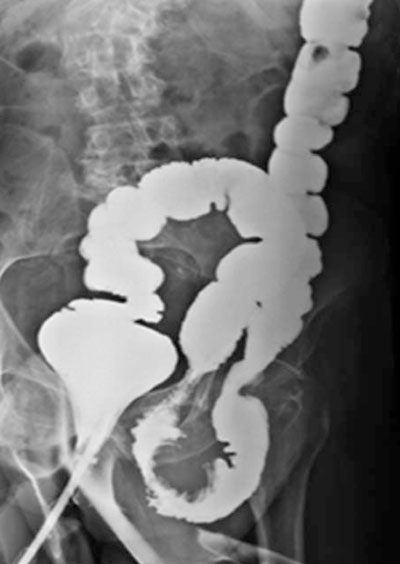

Hernia inguino escrotal bilateral, irreductible. A nivel de la hernia izquierda se palpó una tumoración pétrea, de 2 por 2 cm aproximadamente, móvil, no dolorosa. Testículo y cordón de características normales. Examen proctológico: no se palparon tumoraciones. Se realizó una ecografía de partes blandas que informó lesión compatible con tumor de colon. Con planteo de cáncer de colon se solicitó un colon por enema que evidenció una lesión estenosamente del sigmoides en la hernia (figuras1y2). Resto del estudio normal.

Figura 2: Colon por enema. Imagen de sustracción en colon sigmoides contenido en la hernia izquierda.